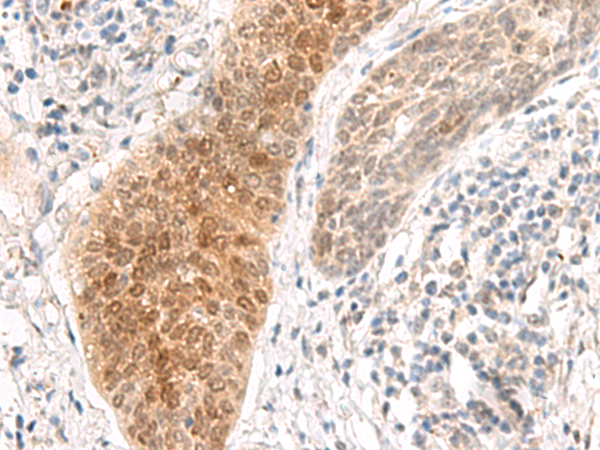

分类: 科研抗体货号: P13457别名: TAMALIN应用: IHC反应种属: Human, Mouse, Rat